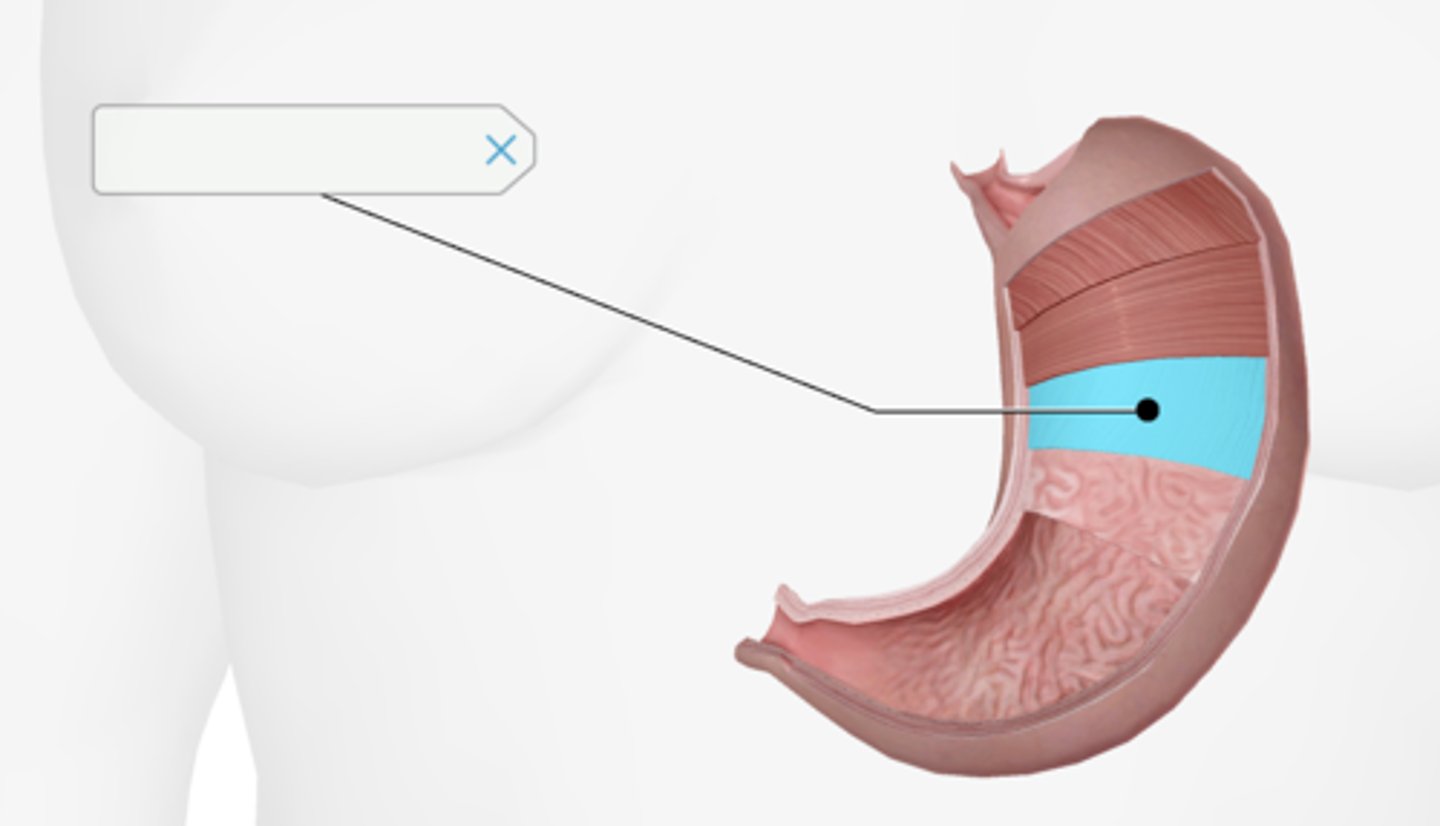

Longitudinal muscle layer of the stomach

Oblique muscle layer of the stomach

Circular muscle layer of the stomach